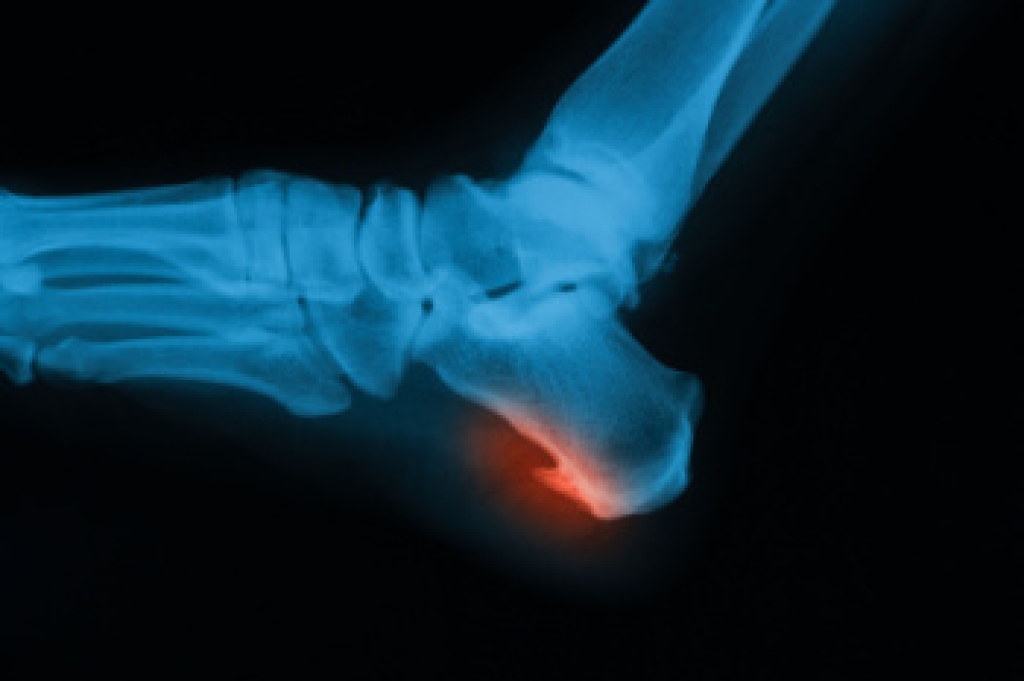

Types of Heel Spurs

Heel spurs are bony growths that develop on the heel bone due to long-term strain on foot muscles and ligaments. They often form where the plantar fascia connects to the heel, causing discomfort and inflammation. Common causes include repetitive stress, wearing improper footwear, and prolonged standing. Risk factors such as flat feet, obesity, and age can increase the likelihood of developing them. There are two main types. Plantar heel spurs located under the heel and dorsal heel spurs form on the back near the Achilles tendon. Symptoms include sharp pain, tenderness, or stiffness. A podiatrist can diagnose heel spurs through an examination and imaging tests, and provide treatments that reduce pain and improve mobility. If you have heel pain, it is suggested that you schedule a visit with a podiatrist for an accurate diagnosis and treatment.

Heel spurs are formed by calcium deposits on the back of the foot where the heel is. This can also be caused by small fragments of bone breaking off one section of the foot, attaching onto the back of the foot. Heel spurs can also be bone growth on the back of the foot and may grow in the direction of the arch of the foot.

Older individuals usually suffer from heel spurs and pain sometimes intensifies with age. One of the main condition's spurs are related to is plantar fasciitis.

Pain

The pain associated with spurs is often because of weight placed on the feet. When someone is walking, their entire weight is concentrated on the feet. Bone spurs then have the tendency to affect other bones and tissues around the foot. As the pain continues, the feet will become tender and sensitive over time.